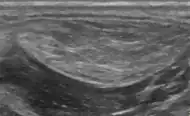

Ultrasonography of a liposarcoma for comparison: In this case a heterogeneous mass consisting of an upper hyperechoic portion, corresponding to lipomatous matrix, and areas of hypoechogenicity corresponding to nonlipomatous components.[24] -